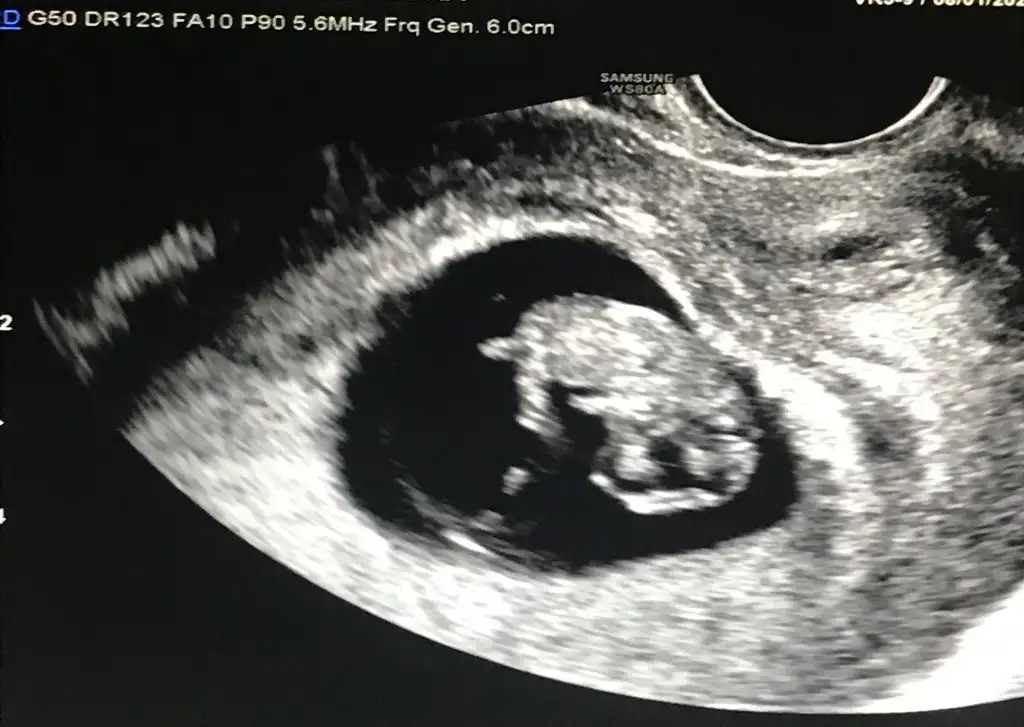

bize de bakabilir misiniz 9 hafta ve 11 hafta vajinal ultrason görüntülerimiz

kuzu senin görüntü ters duruyor biraz zor tahminde bulunmak ama bence erkekbize de bakabilir misiniz 9 hafta ve 11 hafta vajinal ultrason görüntülerimiz

kuzum sanki erkek gibiMerhaba benimde 11 haftalik karindan benim bebegimede bakarmisin teyzesi